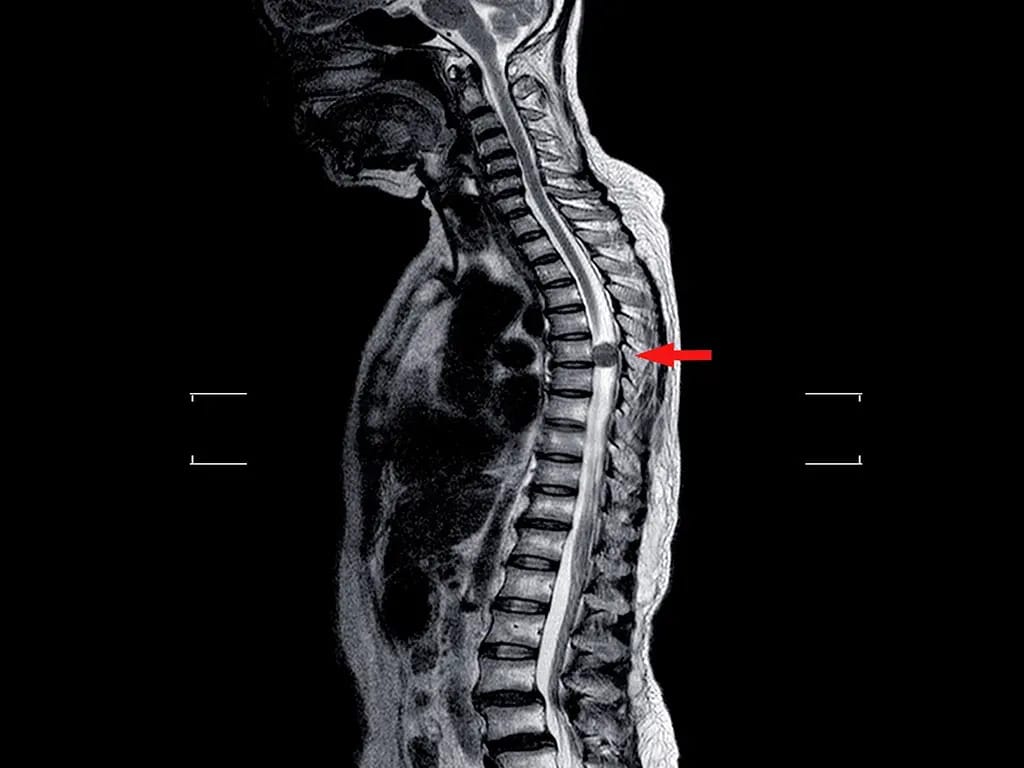

Pesquisadores da UFRJ desenvolveram um medicamento 100% nacional

que permitiu que quatro pacientes paraplégicos voltassem a apresentar movimentos.

Lesão medular sempre foi tratada como sentença definitiva.

Agora, essa ideia começa a ruir.

Lesões medulares estão entre os maiores desafios da Medicina moderna:

dano neurológico complexo

regeneração limitada

pouca resposta a terapias tradicionais

O que esse estudo mostra é simples e poderoso:

o sistema nervoso pode responder quando a ciência é bem feita.

É sobre reabrir caminhos neurológicos que a Medicina havia desistido de explorar.